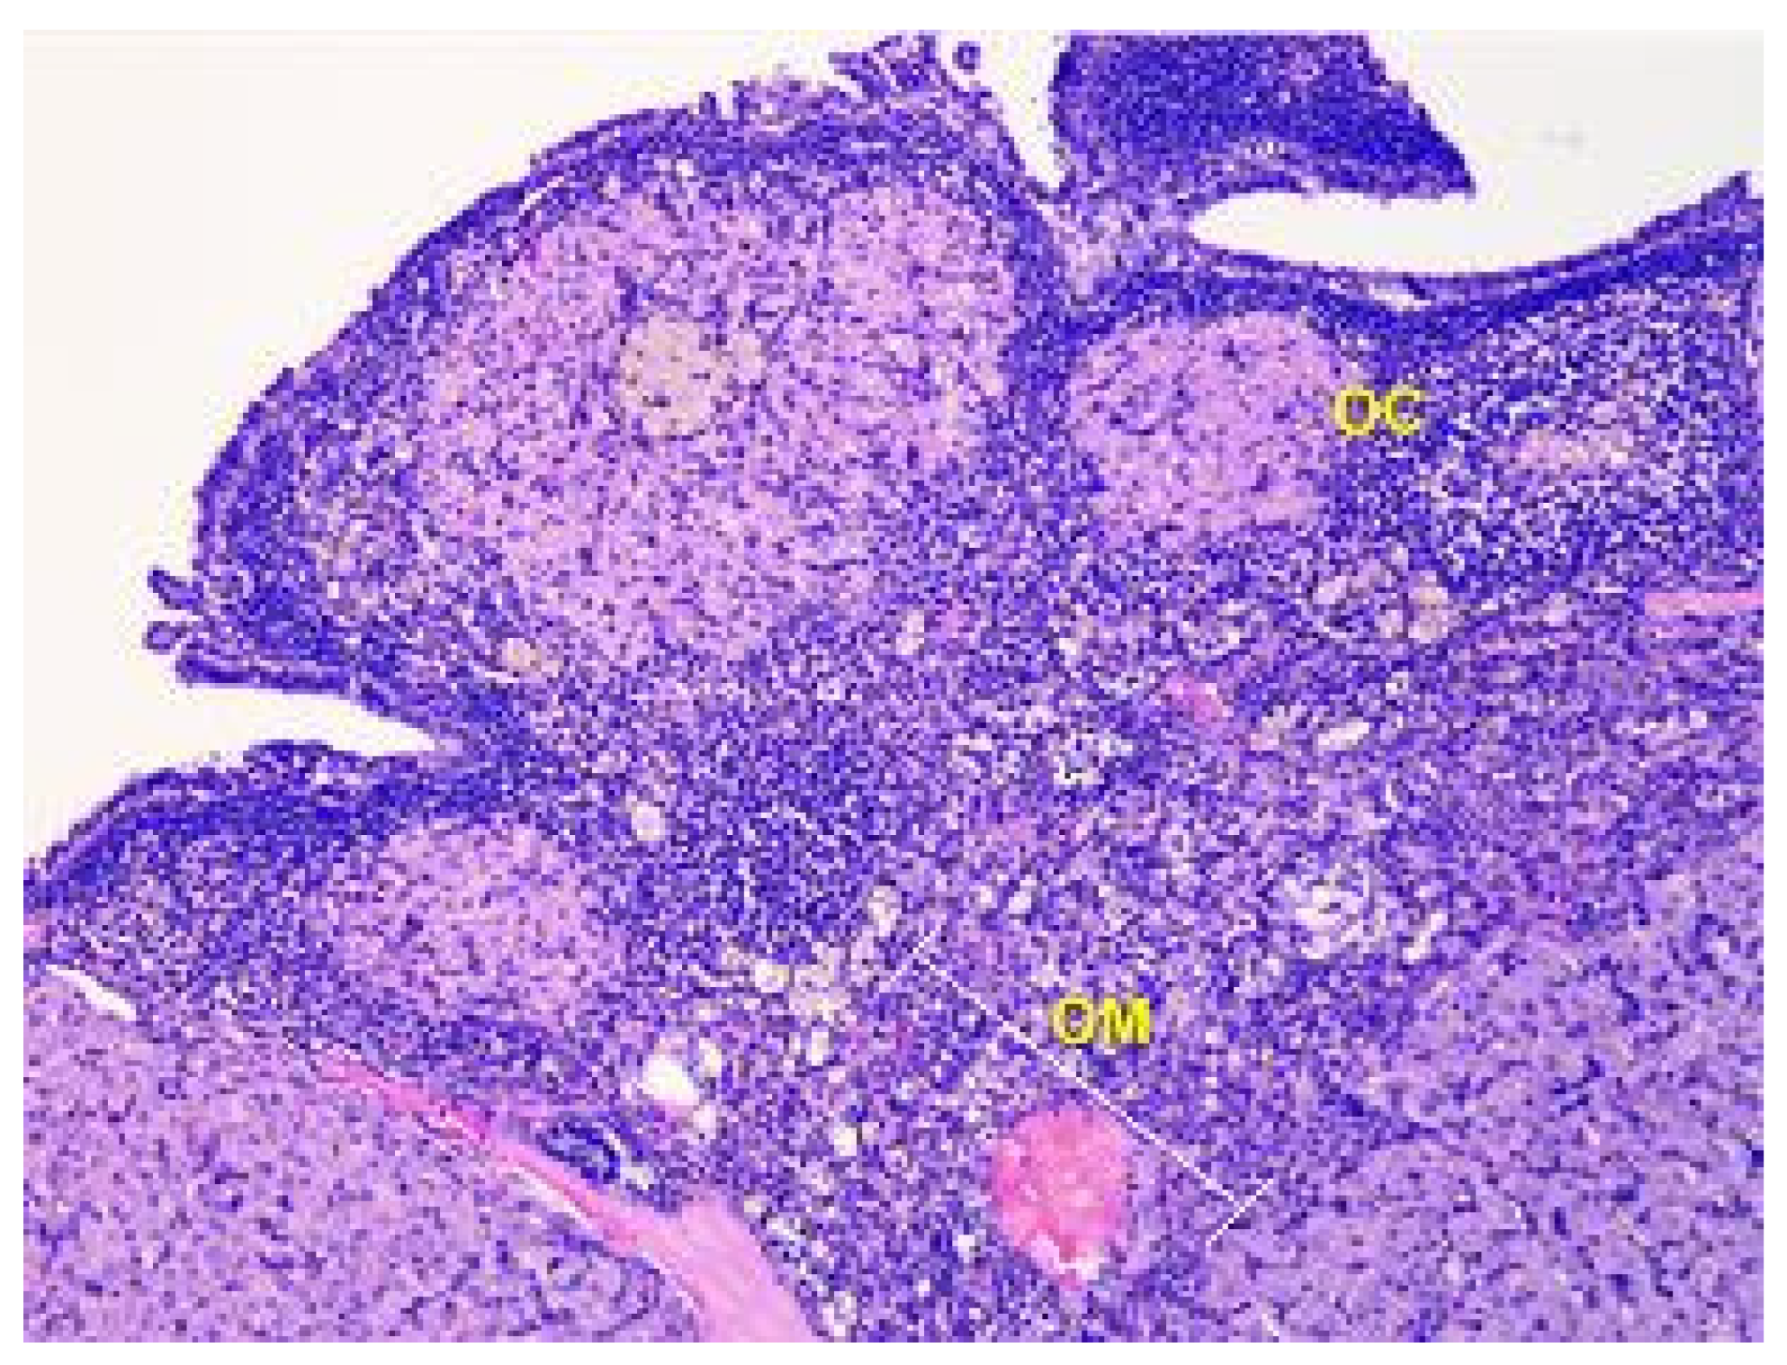

- Denefil, O.V.; Bilyk, Y.O.; Chorniy, S.V.; Fedoniuk, L.Y.; Chornii, N.V. The peculiarities of morpological changes of rats’ ovary and biochemical state under the damage with different doses of lead acetate. Wiad Lek. 2022, 75, 377–382. [Google Scholar] [CrossRef] [PubMed]